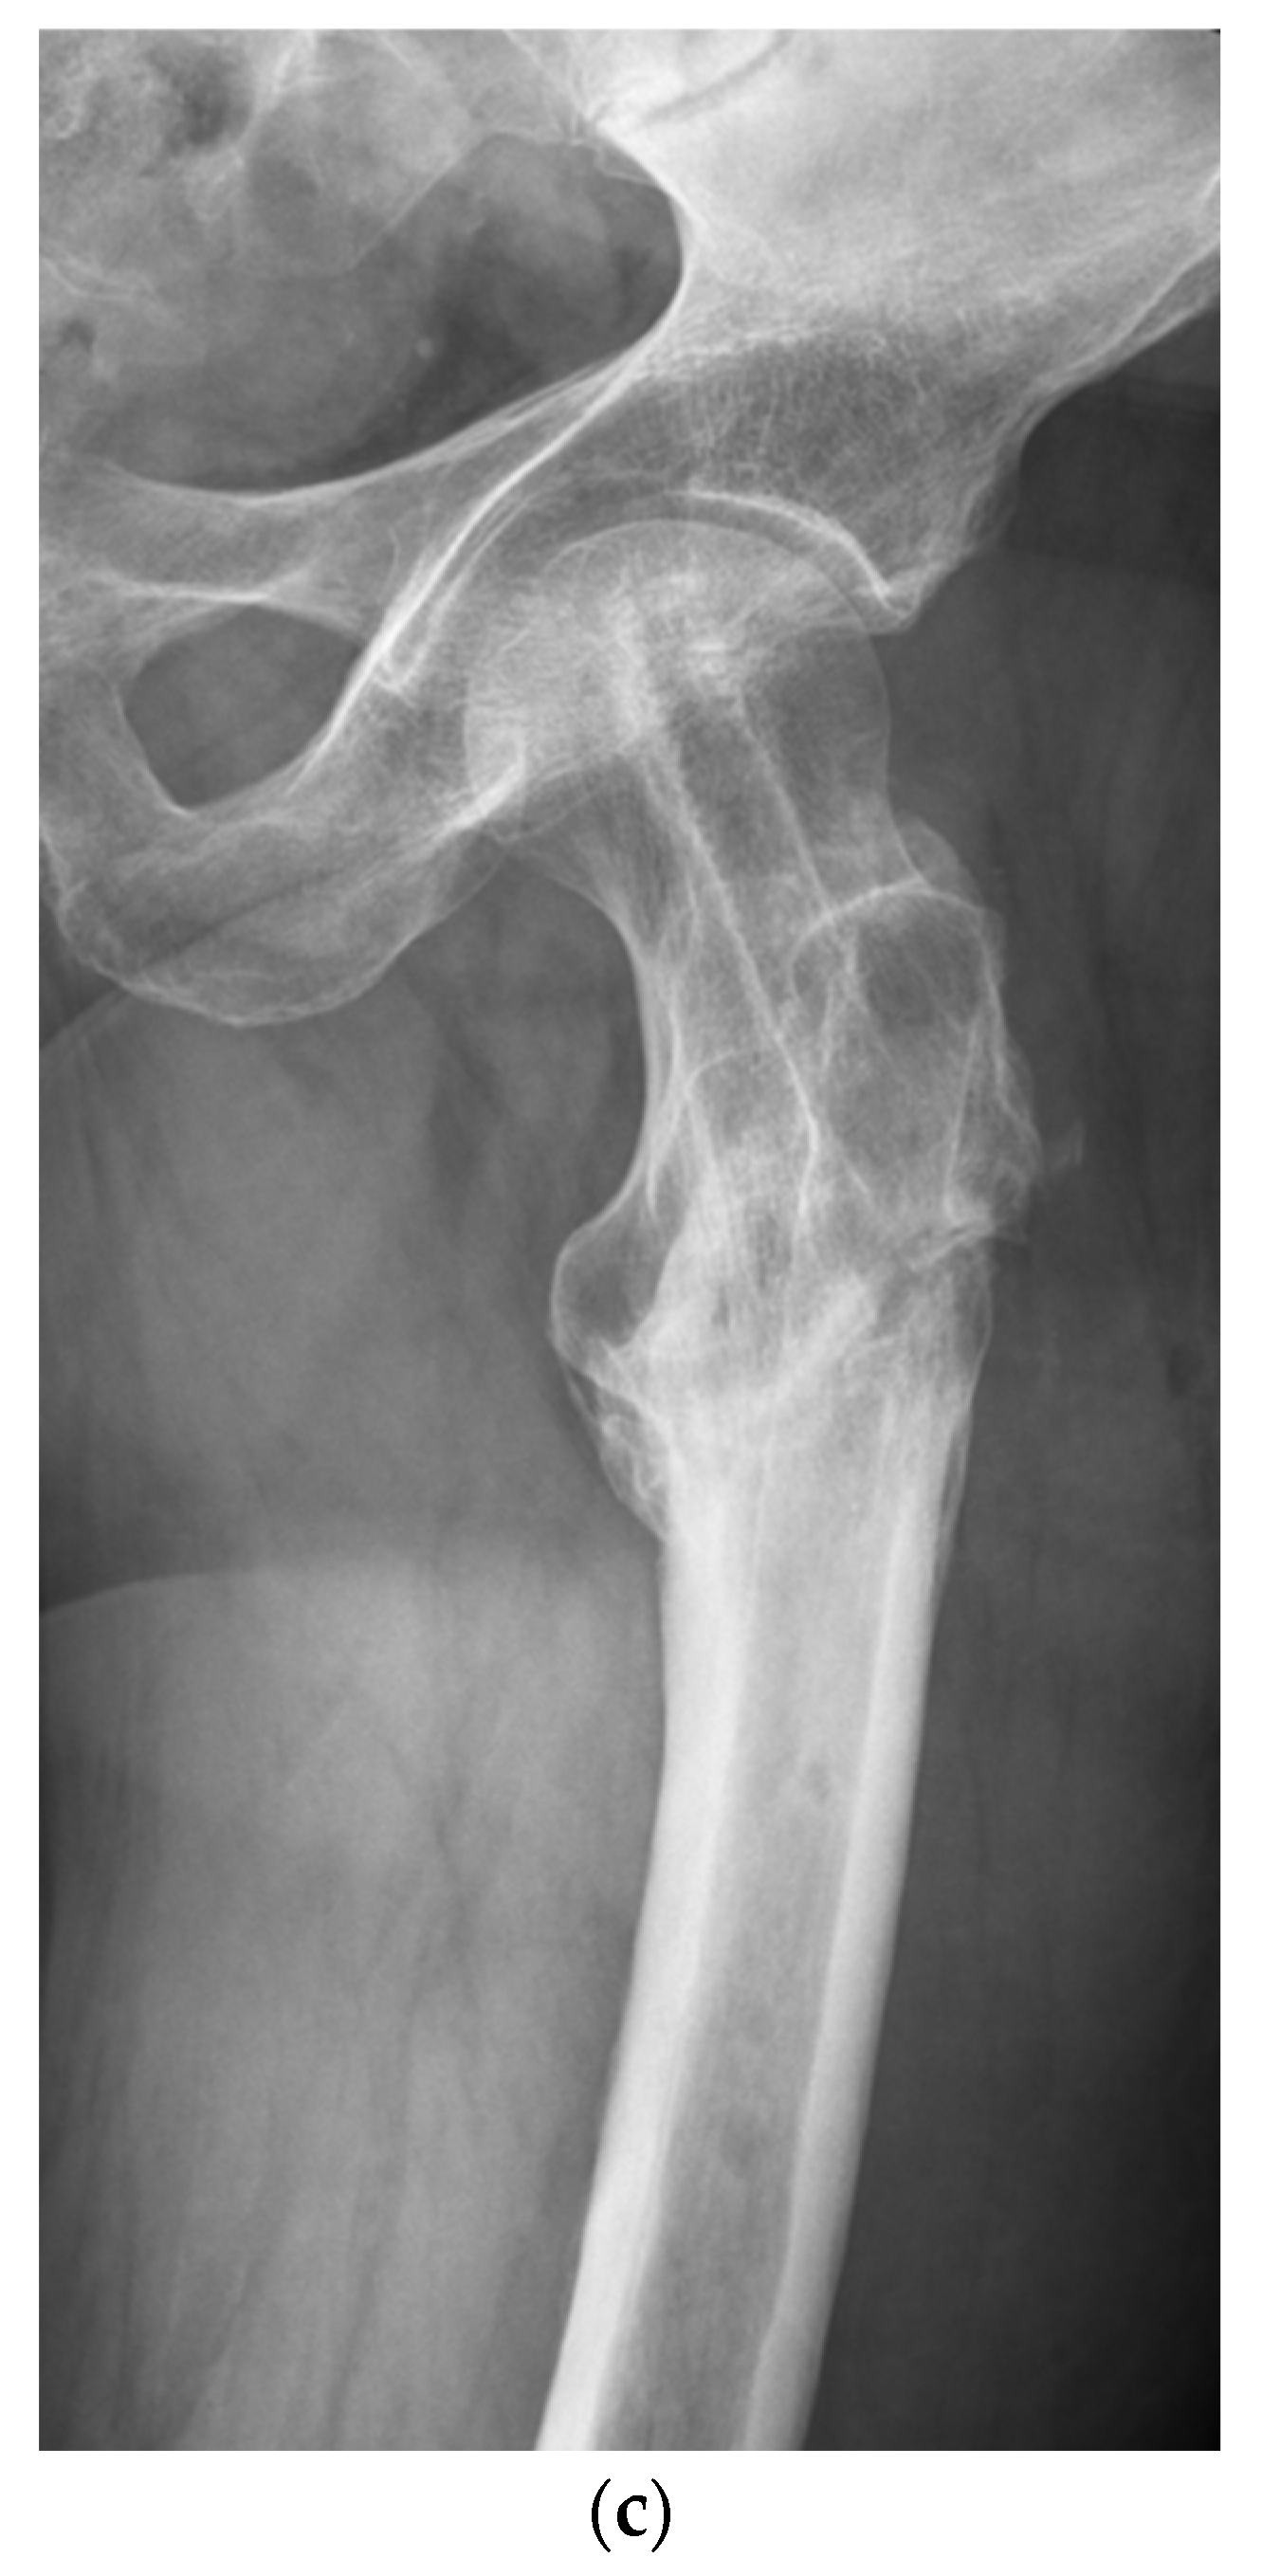

Functional and Radiological Results Following Revision Blade Plating and Cephalomedullary Nailing in Aseptic Trochanteric and Subtrochanteric Nonunion

2.2. Surgical Procedures